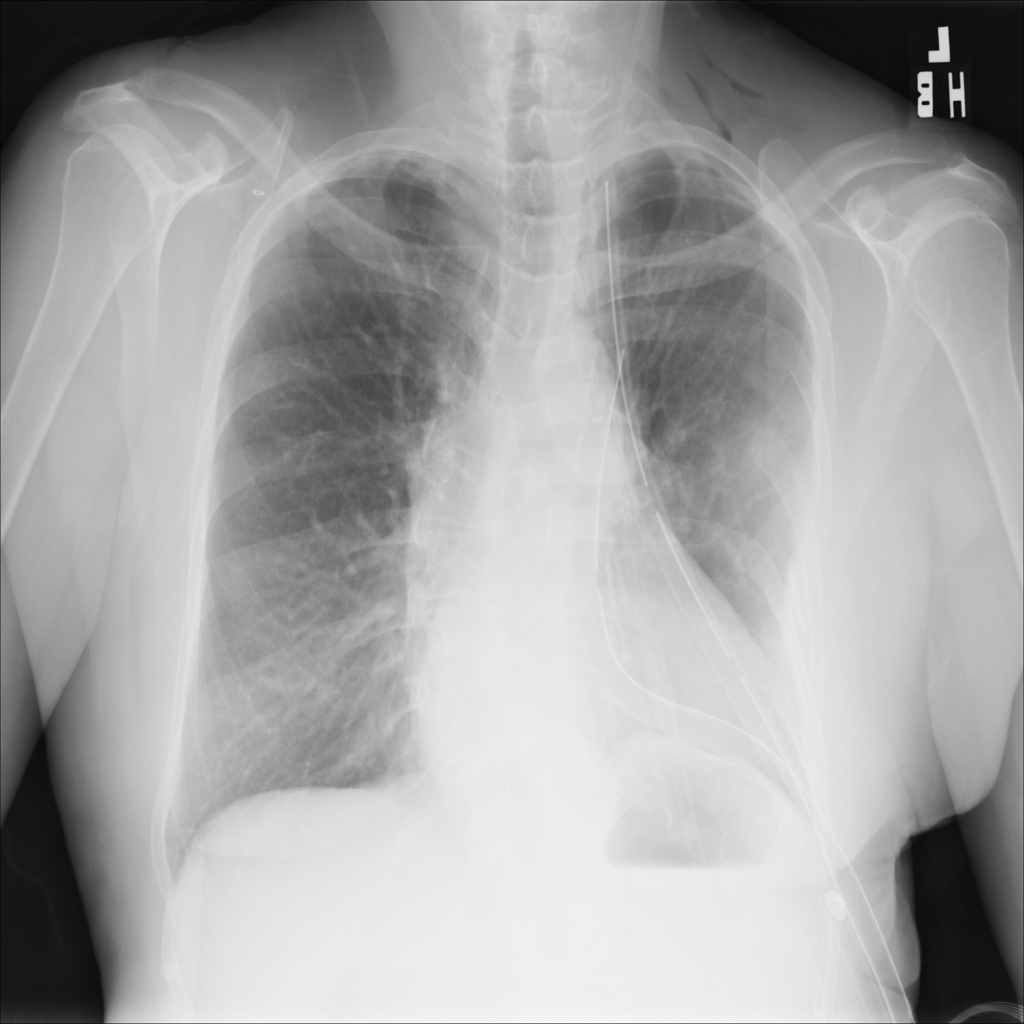

PAT-B0DB · IMG-003Emphysema

PAT-B0DB · IMG-003

PA